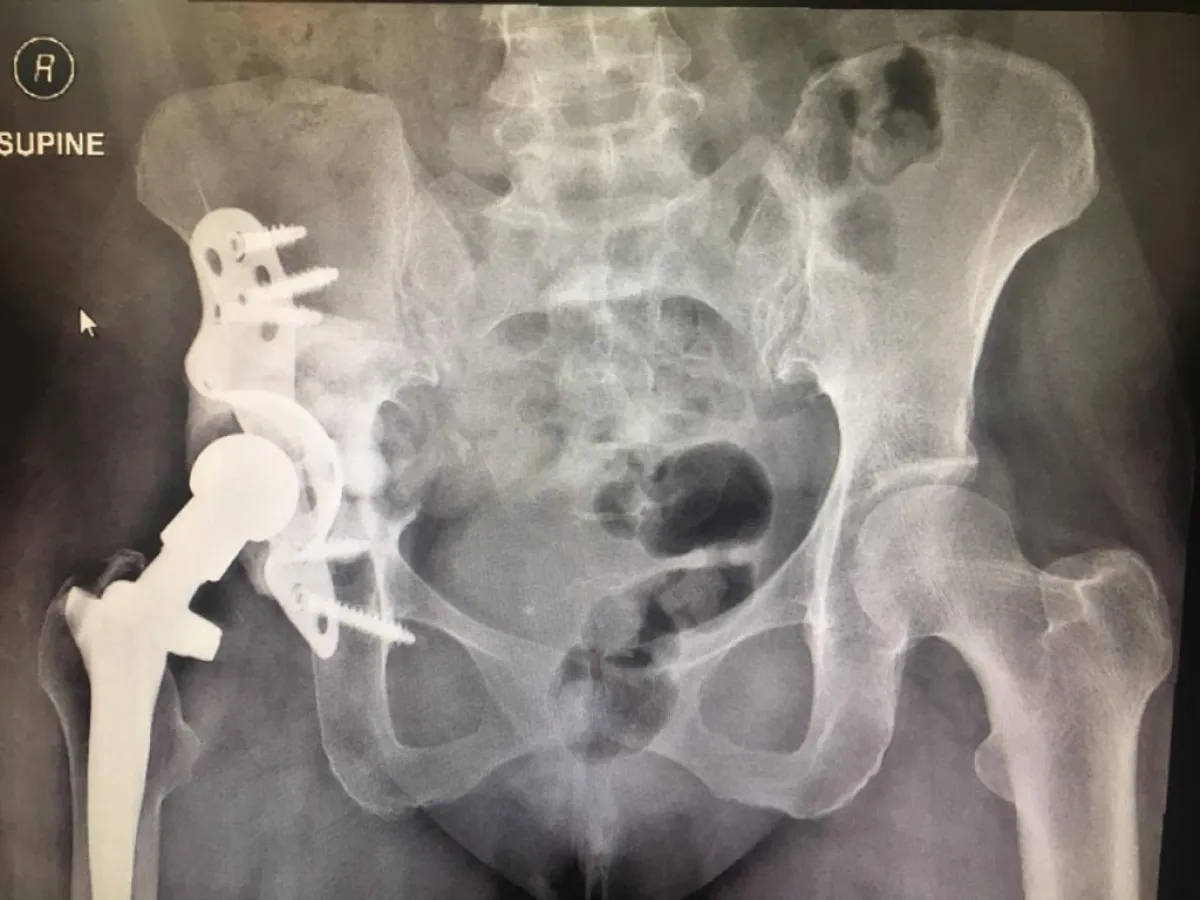

تماثلت مريضة سعودية تبلغ من العمر ٥٣ سنة بفضل من الله ، بعد نجاح أطباء واستشاريو جراحة العظام في مستشفى شرق جدة في تركيب و تثبيت مفصل الورك باستخدام الدعامات والشرائح اللازمة والتطعيم العظمي، حيث كانت المريضة تعاني من عدم القدرة على المشي ومن الآلام المستمرة في مفصل الورك الأيمن، وكانت قد أجريت لها عملية استبدال مفصل قبل ١٦ سنة ، و بعد معاينة و فحص الأطباء بمستشفى شرق جدة لحالة المريضة أظهرت الأشعة المقطعية التي أجريت لها قبل العملية وجود تخلل في المفصل القديم من جهة الورك و تحرك لمفصل الورك داخل الحوض مع تآكل في العظم ، و هذا ما دعى الأطباء إلى إجراء هذه العملية .

و أوضح المدير الطبي بمستشفى شرق الدكتور عباس الشيخ أن هذا النوع من العمليات الجراحية يُعد بالغ الصعوبة نظراً لندرتها ولحاجتها لبعض التجهيزات الطبية و الجراحية الدقيقة، مما يتطلب معه إجرائها في مراكز تخصصية متقدمة في إجراء عمليات تبديل المفاصل، إلا أن وزارة الصحة تحرص على توفير كل ما يلزم لإجراء مثل هذه العمليات المتقدمة، وقد تمكن المستشفى بفضل الله و توفيقه ثم بجهود منسوبي قسم العظام من إجراء هذه العملية بنجاح تام بفضل الله، وعودتها إلى أسرتها وذويها وتمكنها من ممارسة حياتها الطبيعية .